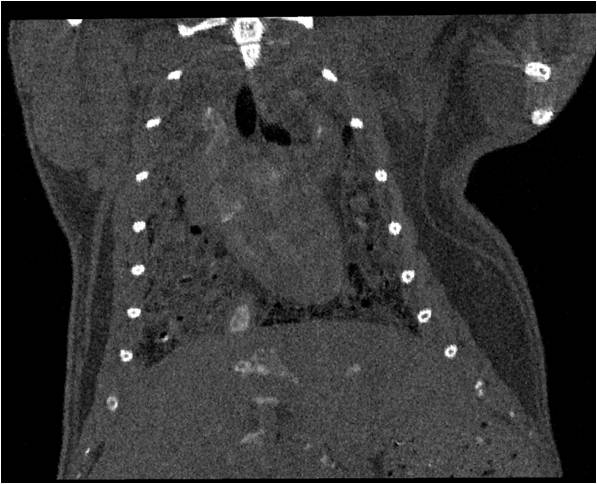

胸部和心血管的層析成像 胸部和心血管的3D圖像